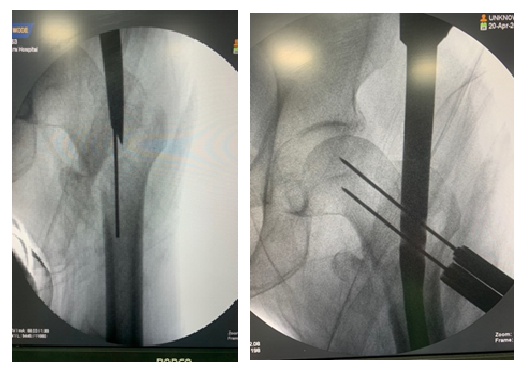

Initially, closed reduction was attempted using internal rotation and longitudinal traction. In cases where closed reduction was not feasible, a mini-open approach was employed. This involved making a small longitudinal incision approximately 5 cm proximal to greater trochanter. Gluteal fascia was incised, and gluteus medius was split longitudinally to access tip of trochanter. The correct entry point for nail was determined using fluoroscopy, and a guide wire was advanced from trochanter to medulla (fig. 2).

Fig. 2: Entry site

Fig. 3: Lag screw guide wire placed close to calcar

Subsequently, a cannulated drill was used to establish an entry point for nail. After drilling the proximal femur, a nail sized at 130° and 240 mm was inserted. Under fluoroscopic guidance, lag screw guides were positioned as near to the calcar as possible on the anteroposterior radiograph and centrally on lateral radiographs (fig. 3).

Once the appropriate location was identified, measurements were recorded. A novel cement inserter device was developed based on diameter of PFNA instrumentation (fig. 4)